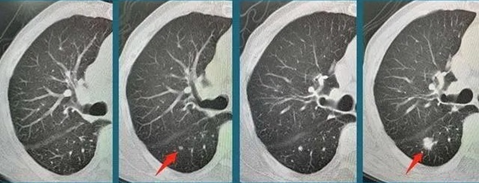

动态观察结节,结节逐渐增大—高危